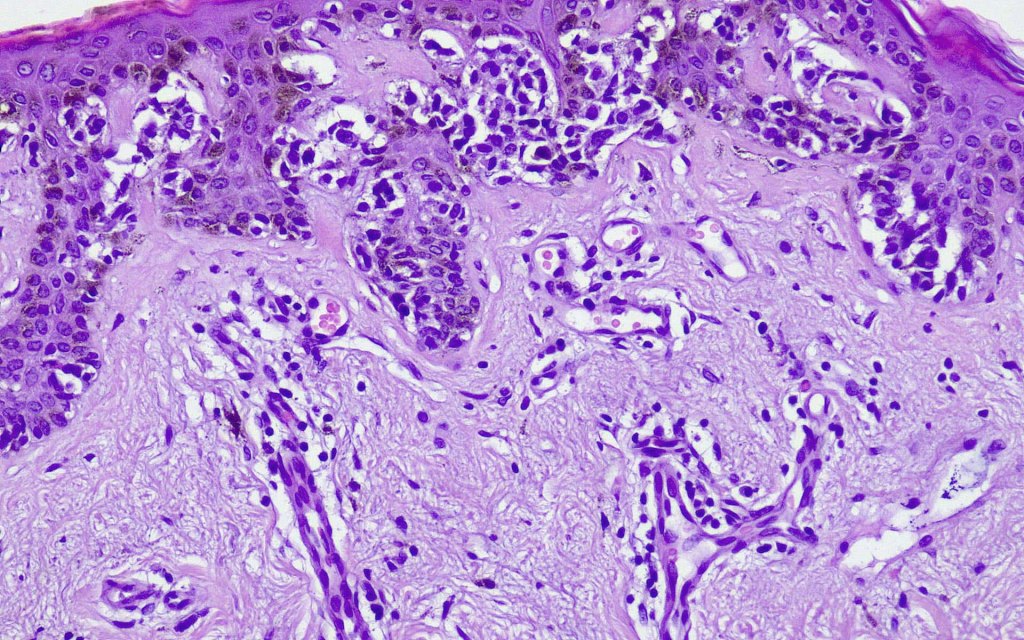

Histological features

- A broad lentiginous proliferation of atypical melanocytes unasscoiated with any loss of the rete ridges

2. Melanocytes generally small, epithelioid (rather than spindled) with either vesicular nuclei and prominent nucleoli or are hyperchromatic.

3. The cells can be present singly, in short pallisades or can extend along a large section of epidermis

4. Pagetoid spread is sometimes seen in more established lesions

5. Grey/greenish cytoplasm (due to fine melanin pigment) occasionally encountered

6. Mitoses are not conspicuous

7. Fibroplasia not seen and elastosis is either mild or absent

8. An invasive component may be present